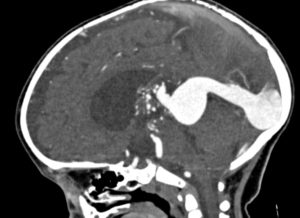

In infants and children, the malformation more commonly presents with neurological symptoms, such as hydrocephalus, macrocephaly, and seizures. VOGM can rarely present in adults, and it typically presents with headache, vomiting, seizures, or subarachnoid hemorrhage [1,11]. Computed tomography (CT) and MRI should be used for comprehensive assessment of the arteriovenous shunt and associated brain changes. CT angiography provides rapid and detailed vascular information, often superior to ultrasound or MRI in depicting both arterial feeders and venous drainage, as demonstrated in the arterial phase images, Figures 4 and 5. MRI is the modality of choice for evaluating the ventricular system and cerebral parenchymal damage, which is important for treatment planning [1].

Figure 4. Sagittal view of cerebral CT angiography of VOGM during the arterial phase [12].